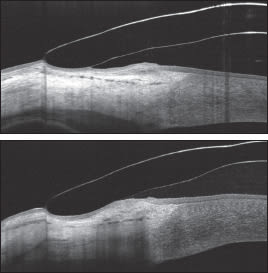

Images 6a and 6b (at right) pair two line scans of the temporal edge of two lenses. Though there was not as significant as a difference in the fluorescein pattern between these two edge profiles, the OCT clearly shows the difference in limbal clearance and desired peripheral bearing of the second lens (bottom image).

Images 6a (top) and 6b. These images pair two line scans of the temporal edge of two lenses.